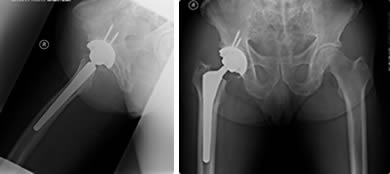

④ 수술적 치료

보존적 치료로 호전되지 않거나 뼈가 괴사되거나 손상이 심할 경우 인공관절 치환술 또는 고관절 절골술 등이 시행됩니다.

고관절 인공관절 치환술의 경우 수술 후 입원 기간은 일반적으로 1~2주이며, 보행기나 목발을 이용한 재활이 약 4~6주간 필요하게 됩니다. 일상적인 회복에는 3~6개월이 소요될 수 있으며, 6개월 정도가 지나면 가벼운 운동도 가능해집니다.

② 수술 비용

고관절 인공관절 수술은 보험 적용 여부와 병원급에 따라 차이가 있지만, 일반적으로 본인 부담 기준으로 150만 원~300만 원대 수준입니다. 비급여 항목이 포함되면 더 높아질 수 있습니다.